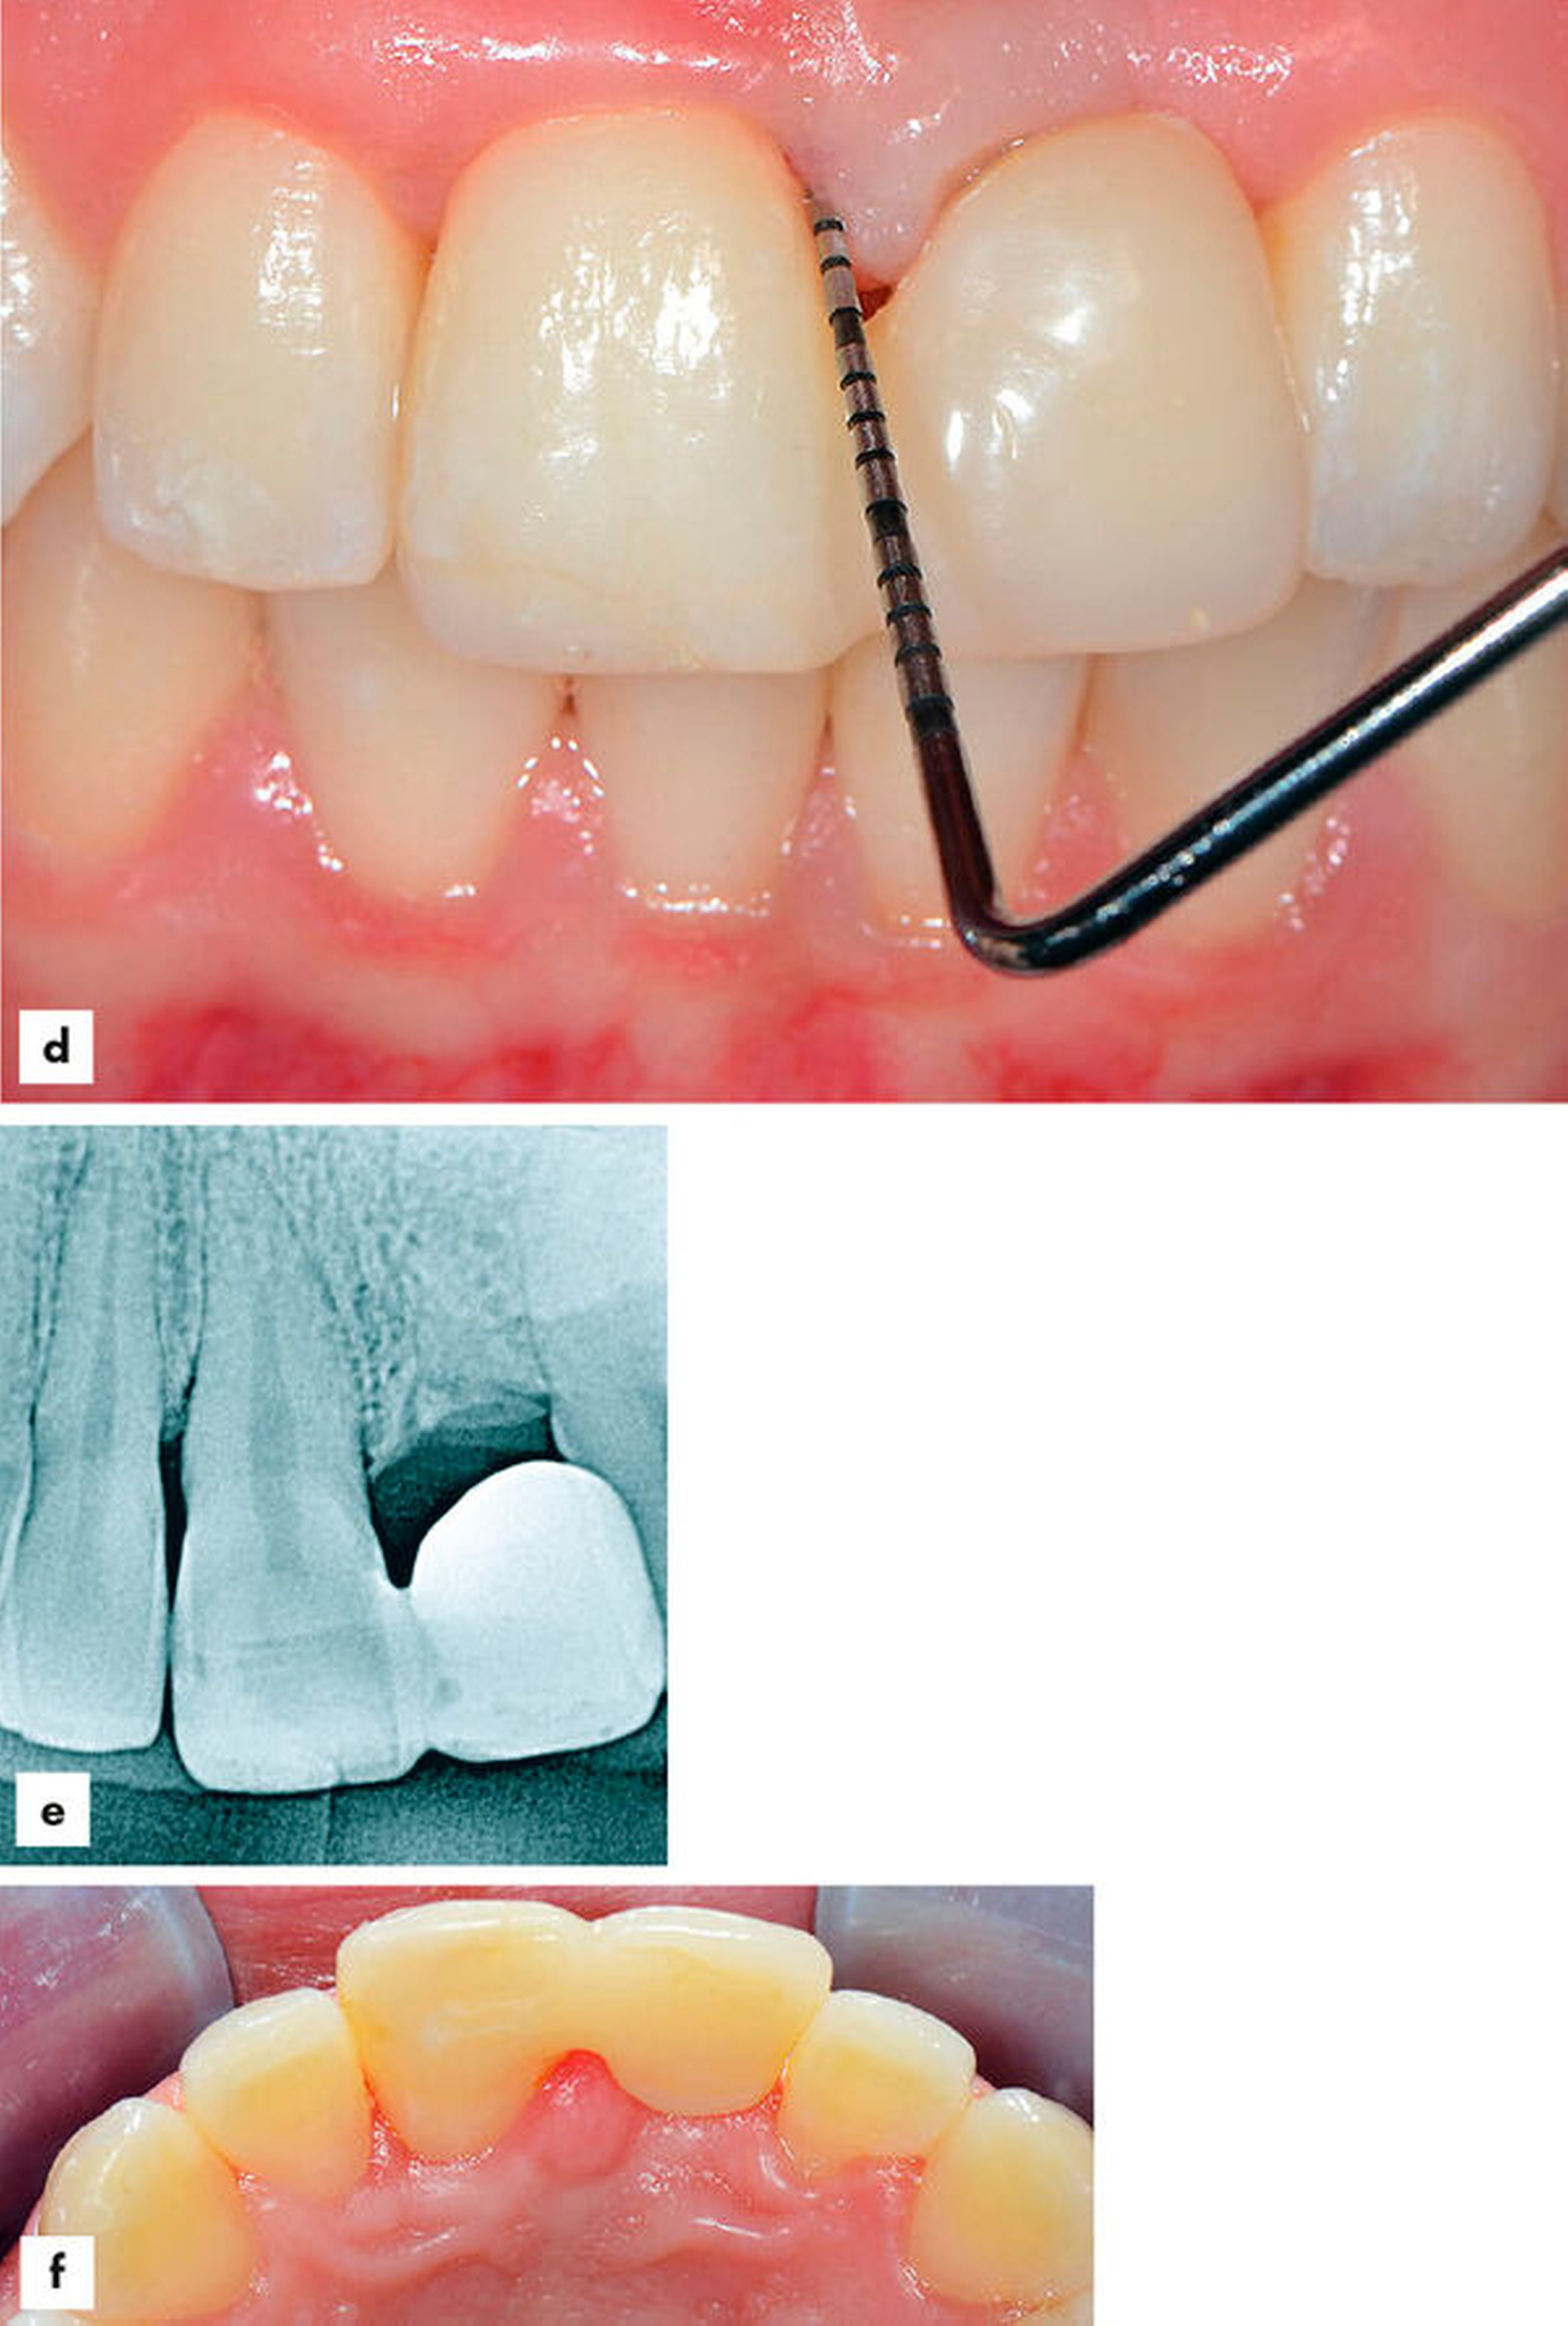

Nach 16 Monaten zeigten sich klinisch entzündungsfreie und reizlose Verhältnisse (Abbildungen 6a–6f). Der Röntgenbefund offenbarte intrakanalikulär eine opake Struktur im Sinne des faserverstärkten Kompositmaterials. Hinweise auf periapikale Veränderungen waren nicht feststellbar (Abbildung 6d). Die Restauration präsentierte sich in einem funktionell und vom Aussehen her guten Zustand ohne jegliche Zeichen endodontischer oder parodontaler Irritationen (Abbildung 6e). Der Patient war zufrieden und nutzte täglich die individuell ausgewählte Interdentalraumbürste (Abbildung 6f).